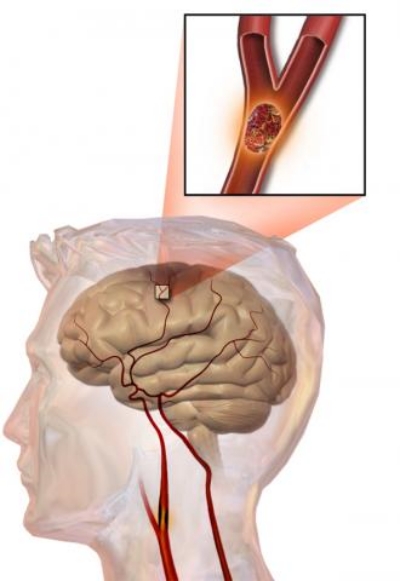

우리나라에서 단일 질환으로 사망률 1위는 뇌졸중이라고 하는데요. 뇌졸중은 뇌의 혈관이 좁아지면서 혈관이 막히며 발생하는 질환입니다.

두통은 뇌경색보다 뇌출혈에서 더 많이 나타나고 평상시에 일반적인 두통이 아니라 강도가 훨씬 셉니다.